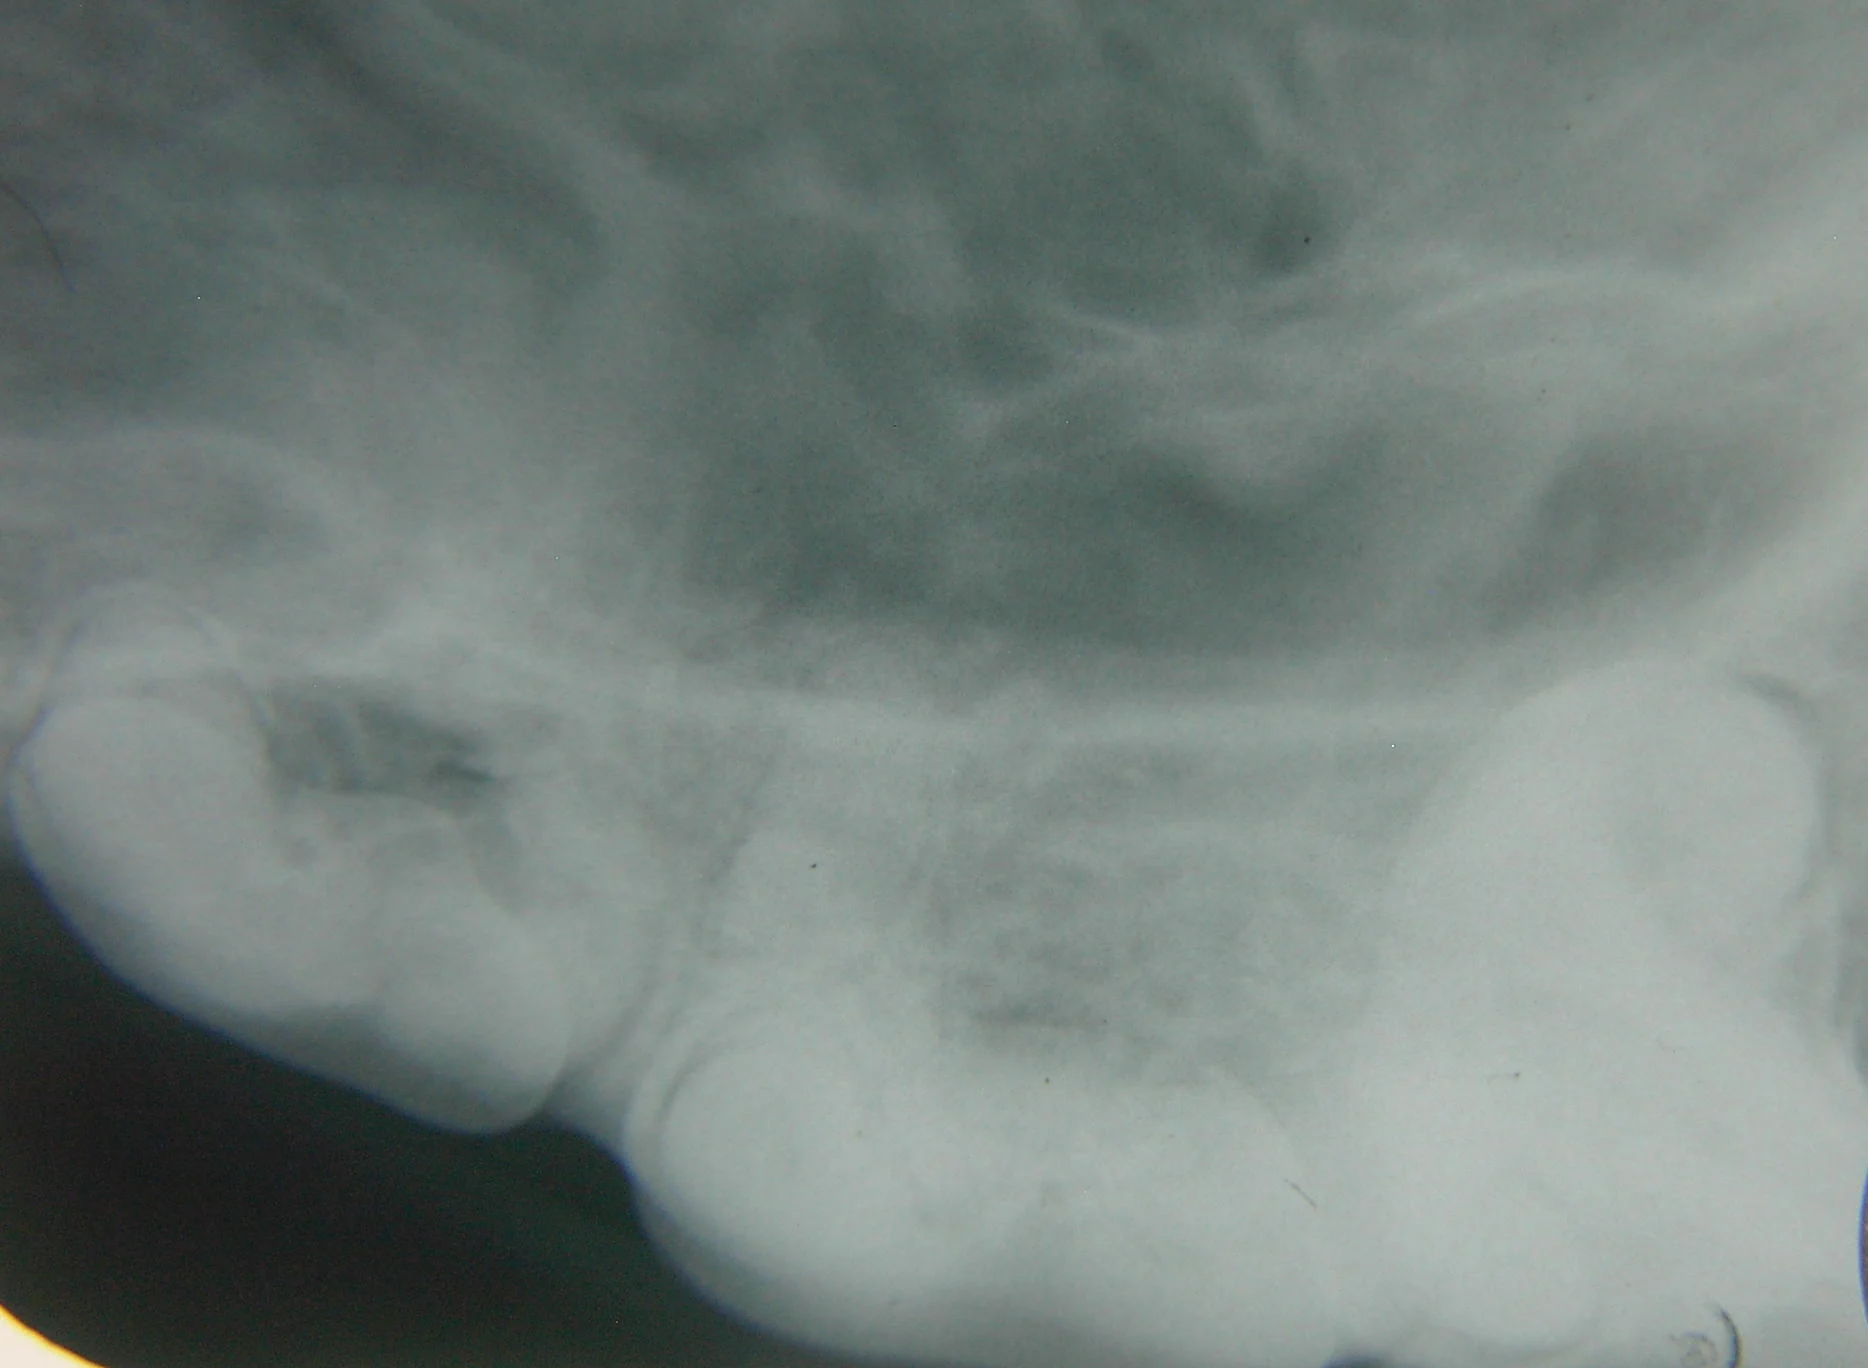

A suborbital swelling or draining tract as seen in this patient would be a good indication for dental radiographs of the maxillary 4th premolar tooth and adjacent teeth.

Suborbital swellings: Look for root tip infection or cystic teeth